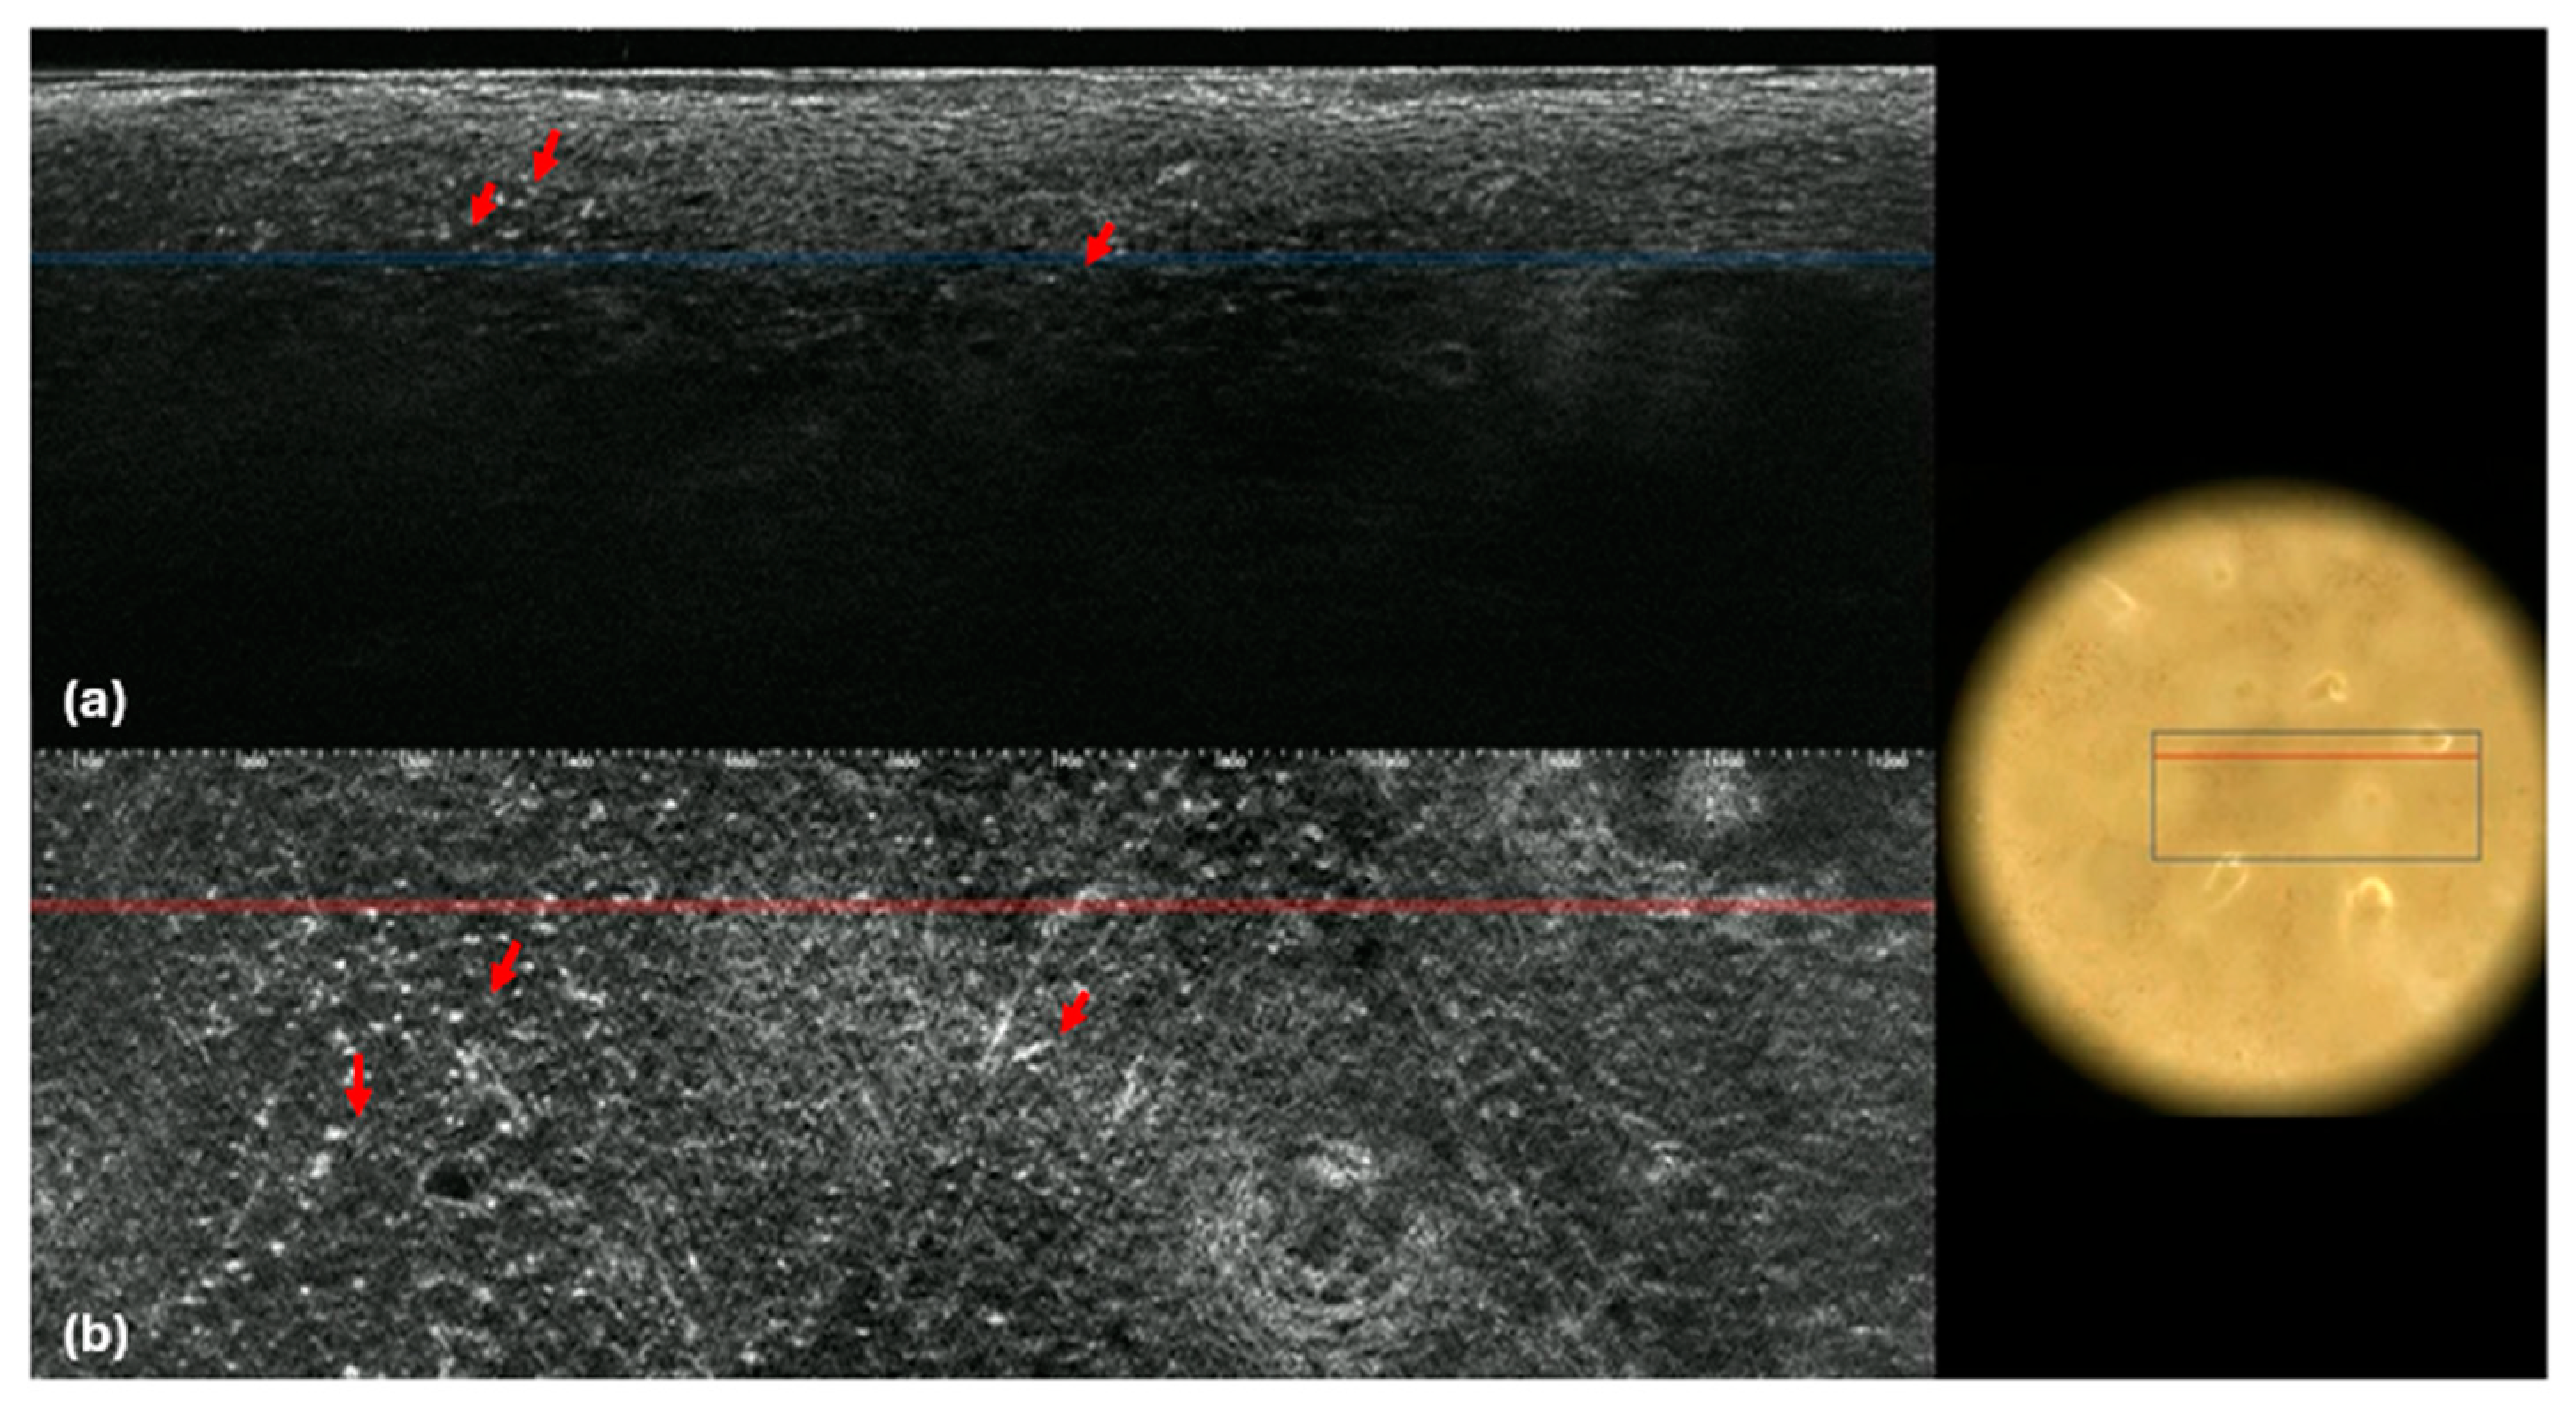

| PCL Criteria | LC-OCT | RCM | p-Value |

|---|---|---|---|

| CTCL | |||

| Epidermis | |||

| Parakeratosis, n (%) | 14 (51.9) | 1 (5.6) | 0.003 |

| Hyperkeratosis, n (%) | 22 (84.6) | 2 (11.1) | <0.001 |

| Epidermal thickness | |||

| Normal, n (%) | 8 (30.8) | 17 (94.4) | Na |

| Atrophy, n (%) | 9 (34.6) | 1 (5.6) | |

| Acanthosis, n (%) | 9 (34.6) | 0 (0) | |

| Epidermal architecture | |||

| Normal, n(%) | 13 (50) | 6 (33.3) | 0.008 |

| Atypical, n (%) | 13 (50) | 12 (66.6) | |

| Epidermotropism, n (%) | 19 (73.1) | 13 (72.2) | 0.686 |

| Pautrier’s microabscesses, n (%) | 1 (3.8) | 4 (22.3) | 0.333 |

| Spongiosis, n (%) | 2 (7.7) | 4 (22.2) | 0.333 |

| Dendritic Cells, n (%) | 1 (3.8) | 6 (37.5) | 0.089 |

| Erosion/Ulceration, n (%) | 3 (11.1) | 0 | Na |

| DEJ | |||

| Interface dermatitis/non-edged papillae, n (%) | 7 (28) | 3 (16.7) | Na |

| Junctional lymphocytes, n (%) | 18 (66.7) | 10 (55.6) | 0.999 |

| Dermis | |||

| Blood vessels dilatation, n (%) | 21 (77.8) | 10 (58.8) | Na |

| Lymphocyte infiltration, n (%) | 14 (51.9) | 11 (61.1) | Na |